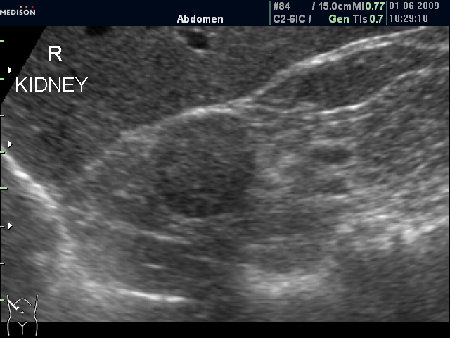

Женщина 72 лет. При УЗИ выявлены два аваскулярные образования: в нижнем полюсе правой почки и у верхнего полюса почки.

Уникальность случая в том, что эти изменения - БЕЗ ДИНАМИКИ с 2005 года.

Опухоль почки?

Без допплера явно опухоль почки